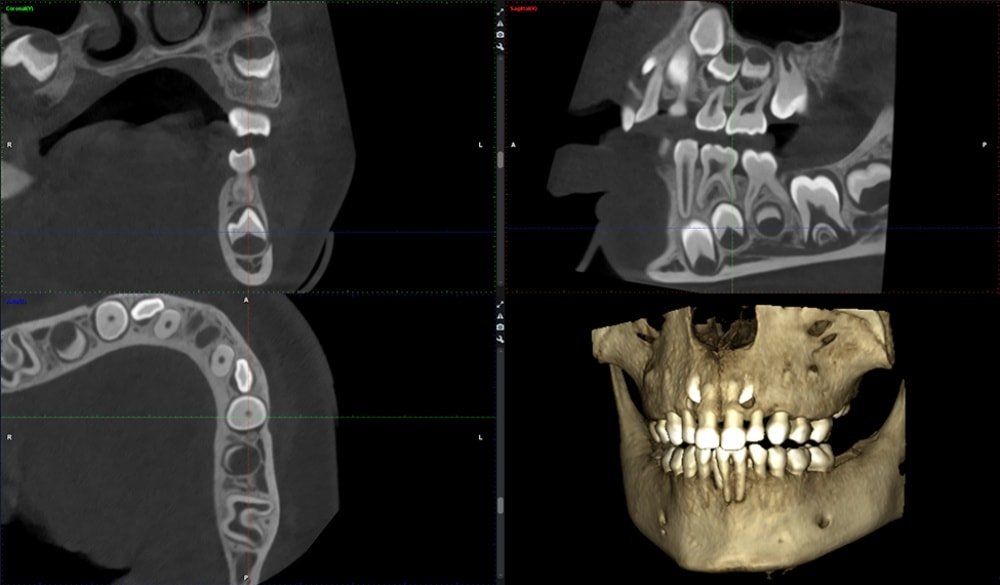

CONEBEAM ou (Scanner)

Le cabinet est équipé d’un appareil de radiographie haute technologie :

un tomographe volumétrique numérique, connu également sous le nom de scanner 3D.

Dans le cas d’un bilan pré-implantaire ou dans le cas de recherche de foyers infectieux, un bilan radiographique 3D est indispensable au docteur Alexandre ORLICK

En une seule prise de cliché 3D, le scanner offre un bilan détaillé.

Il permet de visualiser en 3 dimensions, l’ensemble de votre massif facial particulièrement les maxillaires et les dents.

Il facilite le diagnostic des maladies parodontales, la planification des implants, les interventions chirurgicales de même que les extractions des dents de sagesse. Il permet également la visualisation de kystes.